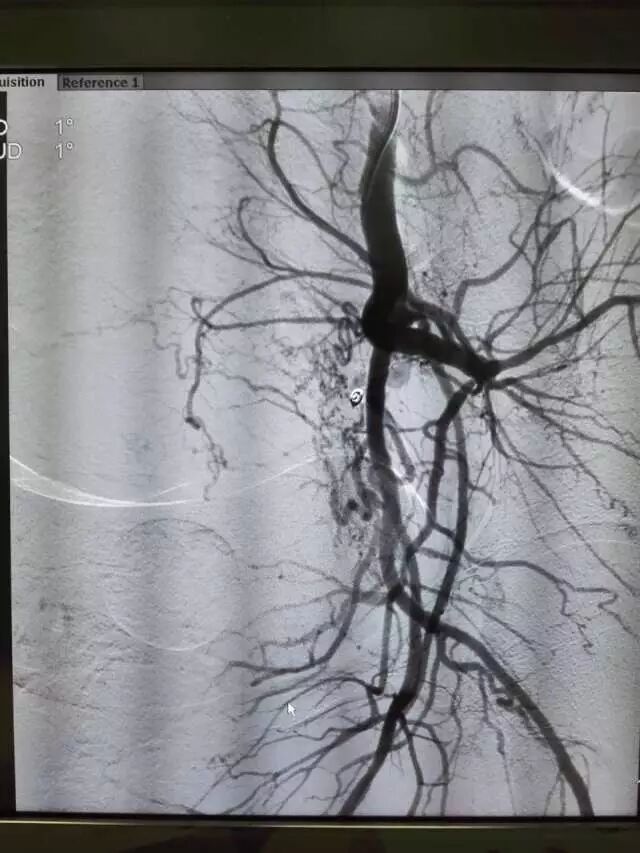

近日,淳安县第一人民医院介入治疗团队实施双侧子宫动脉栓塞术成功抢救一名大出血产妇。

医院产科抢救小组专家经过会诊分析后,考虑到患者年纪较轻,应尽可能保全子宫。随即,抢救小组果断决定马上送介入治疗中心实施双侧子宫动脉栓塞术。

全体抢救人员争分夺秒,利用DSA这项新技术进行选择性插管造影,成功找到了出血的部位,并及时用明胶海绵和弹簧圈栓塞了双侧子宫动脉,术后造影不再出血,患者终于转危为安。整个手术持续了近5个小时,在成功挽救了患者生命的同时,也为患者保全了子宫。